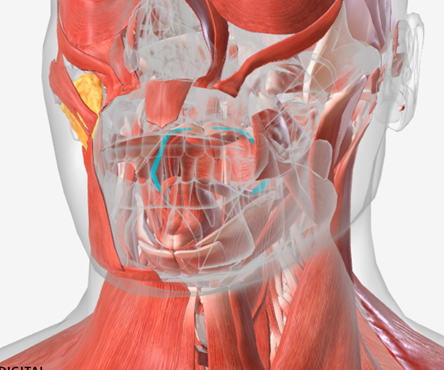

Superior pharyngeal constrictor

origin is on the pterygomandibular raphe, coursing posteriorly to insert on the median raphe of the pharyngeal aponeurosis function is to pull the pharyngeal wall forward to constrict the pharyngeal diameter

Middle pharyngeal constrictor

origin is on the horns of the hyoid and stylohyoid ligament, coursing up and back to the median pharyngeal raphe; function is to narrow the diameter of the pharynx

Inferior pharyngeal constrictor

origin is the oblique line of the thyroid laminae, coursing up and back to insert on the median pharyngeal raphe; function is to reduce the diameter of the lower pharynx

Cricopharyngeus

origin is the cricoid cartilage, coursing back to the orifice of the esophagus; function is to constrict the superior orifice of the esophagus; also referred to as the upper esophageal sphincter

Stylopharyngeus

origin is the styloid process, coursing down to insert into the pharyngeal constrictors and the posterior thyroid cartilage; function is to elevate and open the pharynx

Stylopharyngeus

A

Styloglossus

B

Stylohyoid

C

Cricopharyngeus

D

Superior pharyngeal constrictor

E

Middle pharyngeal constrictor

F

Pharyngeal raphe

G

Inferior pharyngeal constrictor

H